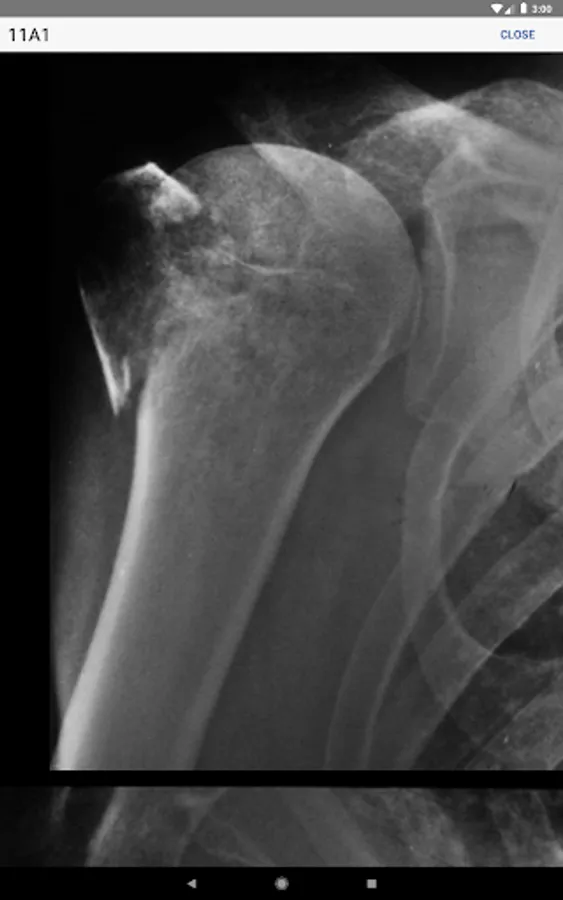

• Information regarding radiological investigations used for classifying a specific fracture

• High-quality, enlargeable x-rays are included